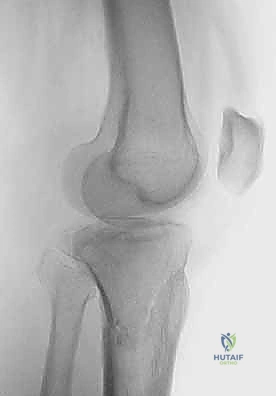

2. التصوير الإشعاعي (X-rays)

الخطوة الأولى هي التقاط صور أشعة سينية من عدة زوايا (أمامية خلفية، وجانبية). تعطي الأشعة السينية فكرة عامة عن وجود الكسر وموقعه، لكنها غير كافية لتقييم الكسور ثنائية اللقمة المعقدة.